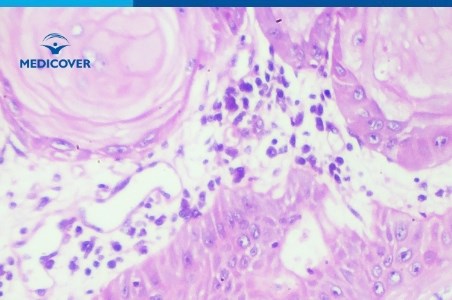

Carcinomul reprezinta peste 80% din numarul total al cancerelor solide diagnosticate in prezent si se dezvolta din celulele epiteliale care intra in alcatuirea tegumentului, cele care intra in alcatuirea mucoaselor sau care captusesc viscerele (organe interne). In mod frecvent carcinoamele se localizeaza la nivelul pielii, al plamanilor, glandei mamare, prostatei, colonului, rinichiului sau...